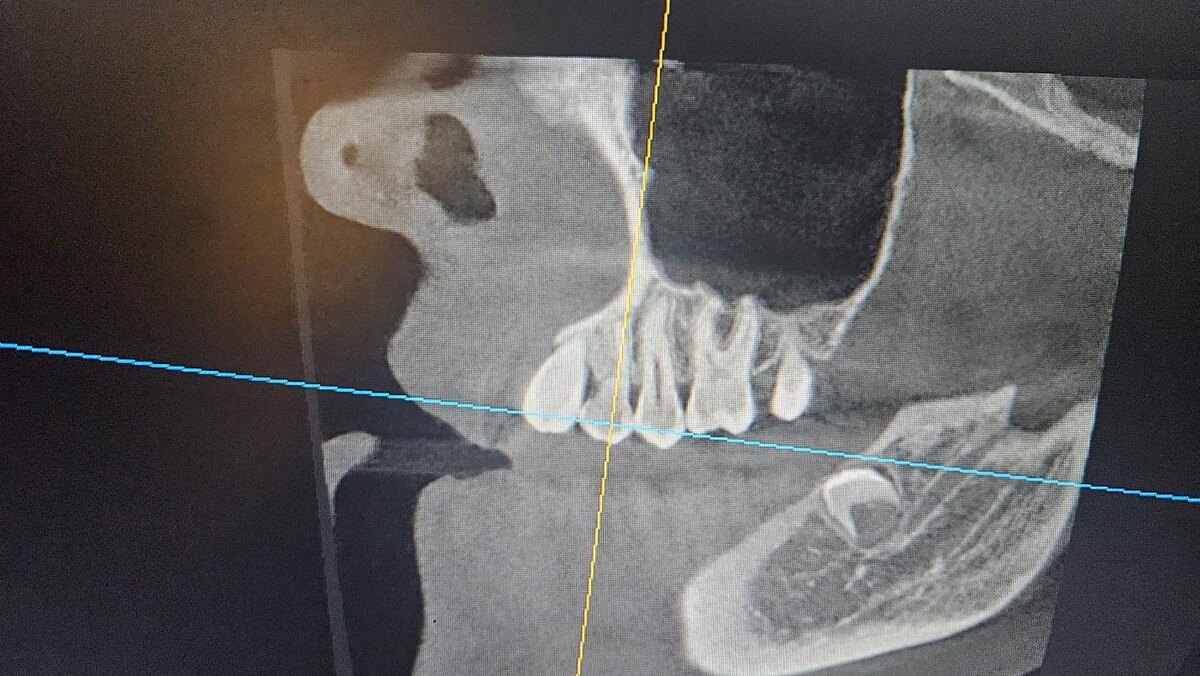

Во время обследования обнаружили у Светланы еще одну проблему — зачатки коренных зубов 3.8 и 4.8 расположены под углом. При такой локализации в челюсти зубы будут прорезываться под наклоном, болезненно и с негативным воздействием на семерки☝️

Зачатки зубов 3.8 и 4.8, которые необходимо удалить

Визуально восьмерки Светланы очень отличаются от зубов мудрости, которые удаляют уже после полного прорезывания. У этих зубов слабый, недоразвитый мягкий корень, который еще не успел кальцинироваться. Это вызывает дополнительные сложности у врача, но является более безопасным вариантом для пациента.